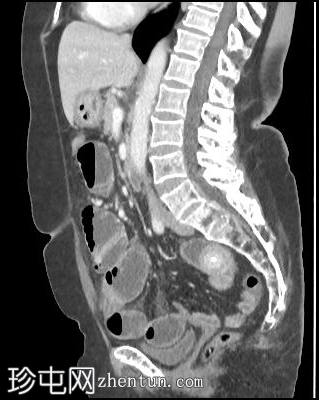

矢状位增强扫描(门静脉期)

5.png

胆囊缩小,囊壁增厚,提示慢性炎症改变。胆囊(底部)与十二指肠(球部)腔之间可见细小瘘管,胆囊内及肝内、肝外胆管内均可见气体(胆道积气)。

远端空肠内嵌顿一枚较大的胆结石(3.5 cm),近端空肠袢扩张,回肠袢、末端回肠及结肠均塌陷。